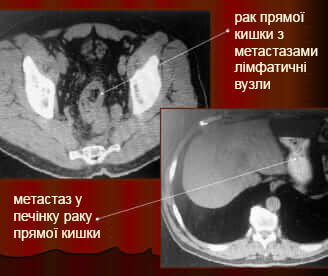

Більшість хвороб можуть призвести до смерті, тому боятися лише раку – це неприпустима помилка. Подивіться знімки органів людей, у яких все почалося з неприємного запаху з рота, сверблячки та кров'янистих виділень із анального отвору відповідно, а закінчилося доповіддю патологоанатома.